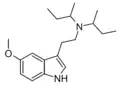

Substituted tryptamines, or serotonin analogues, are organic compounds which may be thought of as being derived from tryptamine itself. The molecular structures of all tryptamines contain an indole ring, joined to an amino (NH2) group via an ethyl (−CH2–CH2−) sidechain. In substituted tryptamines, the indole ring, sidechain, and/or amino group are modified by substituting another group for one of the hydrogen (H) atoms.

| DSBT | artificial | H | CH(CH3)CH2CH3 | CH(CH3)CH2CH3 | N,N-disecbutyltryptamine | |